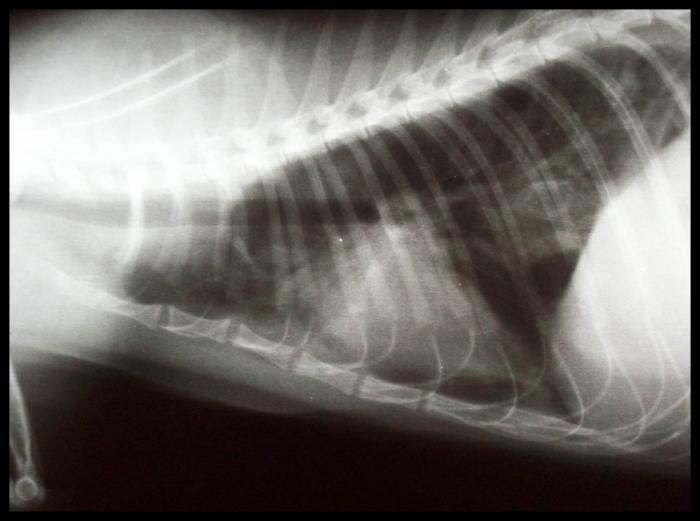

Debe llevarse a cabo con un animal estabilizado y con respiración normal (es decir, jamás con un paciente disneico o cuya oximetría de valores por debajo de lo normal). Es el método más práctico para evaluar tanto continente como contenido de la cavidad torácica, siendo conveniente solicitar al menos dos incidencias (por lo general se realiza laterolateral izquierdo o derecho y dorsoventral o ventrodorsal según el paciente lo permita). Así, se evalúa no solo si existe alguna alteración puntual de la cavidad sino también qué hemitórax se encuentra más afectado, si lo hubiera. Este método permite observar, aparte de la existencia de colectas, fracturas de costilla, rupturas diafragmáticas, presencia de masas, desviaciones viscerales, cuerpos extraños, agrandamiento de la silueta cardíaca o alteración de los patrones vasculares. Los signos radiológicos de colecta de aire son los siguientes: retracción de uno o ambos pulmones con respecto de la pared torácica, mayor densidad del pulmón debido a su colapso, desplazamiento dorsal de la silueta cardíaca.

En el caso de colectas líquidas se hallan: fisuras interlobares ensanchadas, con aumento de densidad de tejidos blandos, retracción del pulmón, quedando un espacio entre este y la pared con radiodensidad similar a los tejidos blandos, redondeamiento de la fisura costofrénica, disminución de visibilidad de la silueta cardíaca y contorno diafragmático poco definido (Figura 3A-B).